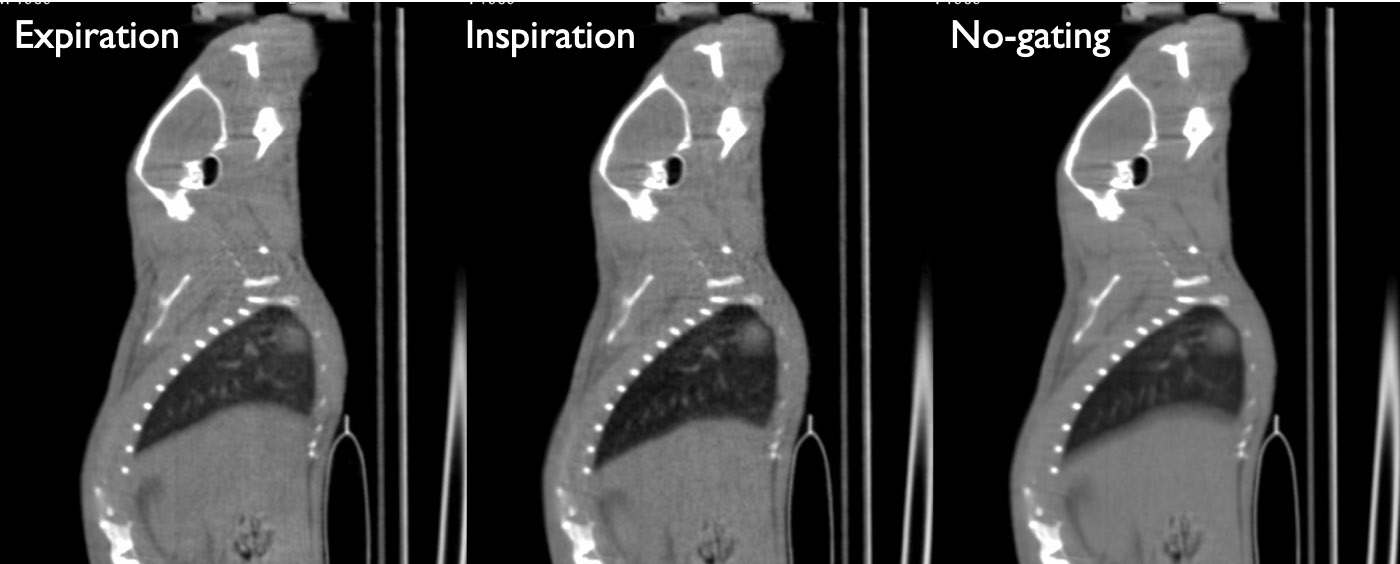

CASE 5: Mouse lung CT imaging

workimg

• Courtesy of: Shanxi Medical University, Tianyuan, China

Research objective: Mouse CT lung imaging with automatic software-based gating, without using any hardware signal

Animal model: Mouse, ~25g, under anesthesia with isofluorane gas

Acquisition protocol: 90 s acquisition time, 65 kVp, 1 mA, 1 bed position

Processing and reconstruction protocol: Image processing into end-inspiration phase and end-expiration phase 0.16 mm isotropic voxel size